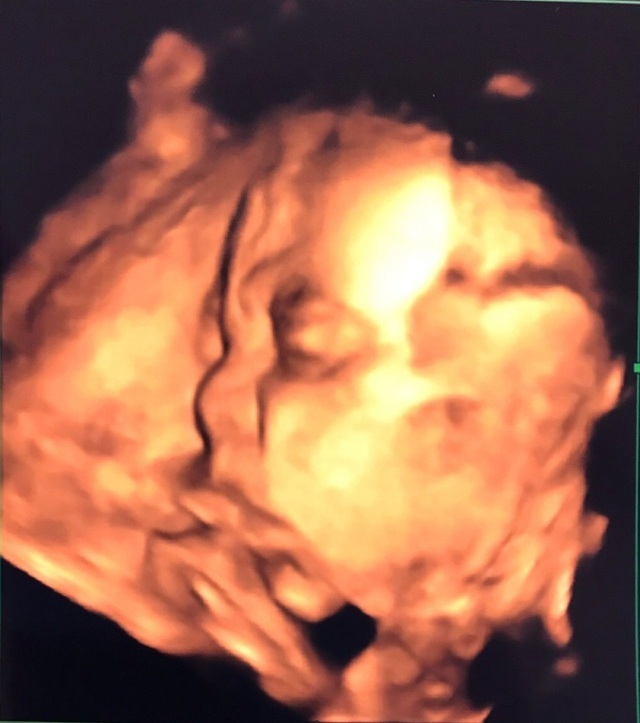

28週2日(28w2d・男の子)|yukarinnn5 さん(32歳)

エコー写真撮影時のエピソード:

検診の度に、どんな顔かな!?と思ってるのに、いつも背中側に顔を向けている息子くん。ようやく顔が見えたけど、やっぱり胎盤に一部くっついていて、これがなんとかとれたベストショット。

妊娠28週で年末を迎え…体重管理に苦労。

お医者さんに、これからケーキも餅も食べるよね!?気を付けて!と…。

年末年始を体重増やさずなんとか乗り越えたのに、そのあとなんの反動か!?仕事始めたら、また増加…。難しい…。